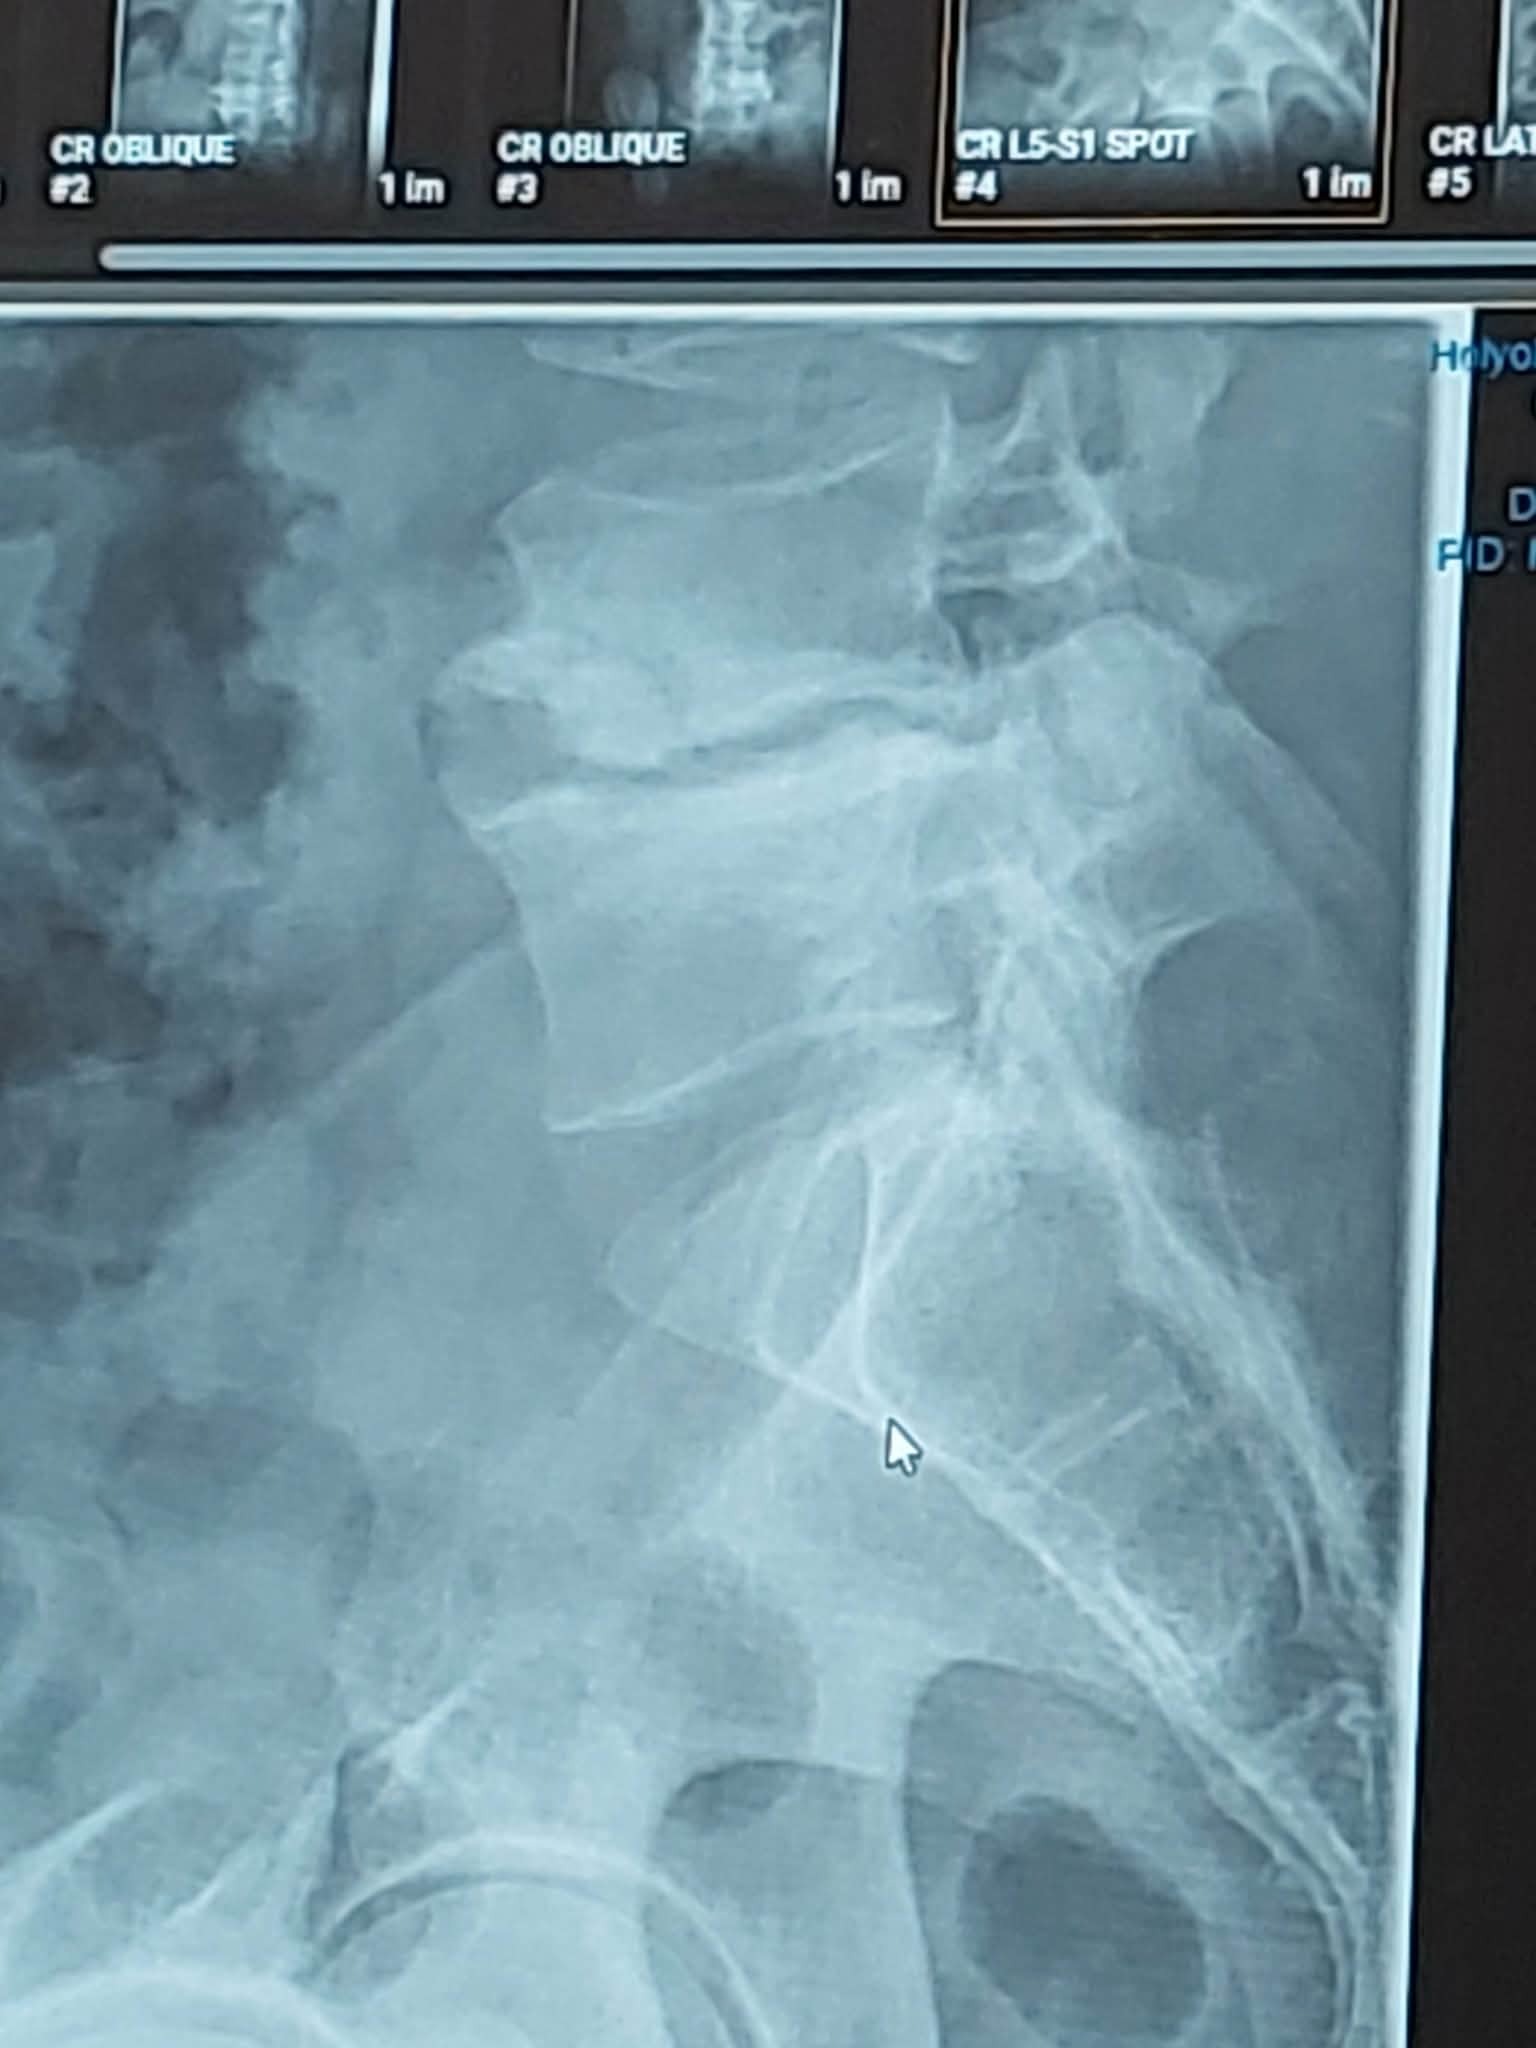

Tanner has been facing some very serious health concerns and recently discovered he needs not 1, but 2 surgies. One is a major procedure to fix his part of back. This is where he really needs support.

This past Oct. I again urged he get another look. That has resulted in Tanner discovering he has no disc between two of his vertebrae in his lower back. It is bone on bone. Tanner does not have pto...sick time...fsa...none of that with his current line of work. As of right now he doesn't even have a place to live. We have been broken up for 6 months....I have agreed to help him through this. He's had to replace his vehicle twice this year...both times wear and tare repairs that would have been more than the cars were worth...so he has no savings left.